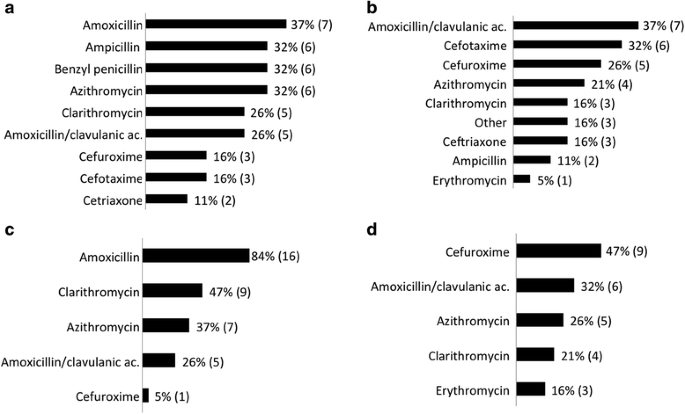

What antibiotics are used to treat pneumonia in toddlers?

For both severe and very severe pneumonia, ceftriaxone was the most commonly prescribed antibiotic after hospitalization (Figure 3). Cefuroxime was prescribed more often for severe pneumonia patients when compared with those who had very severe pneumonia.